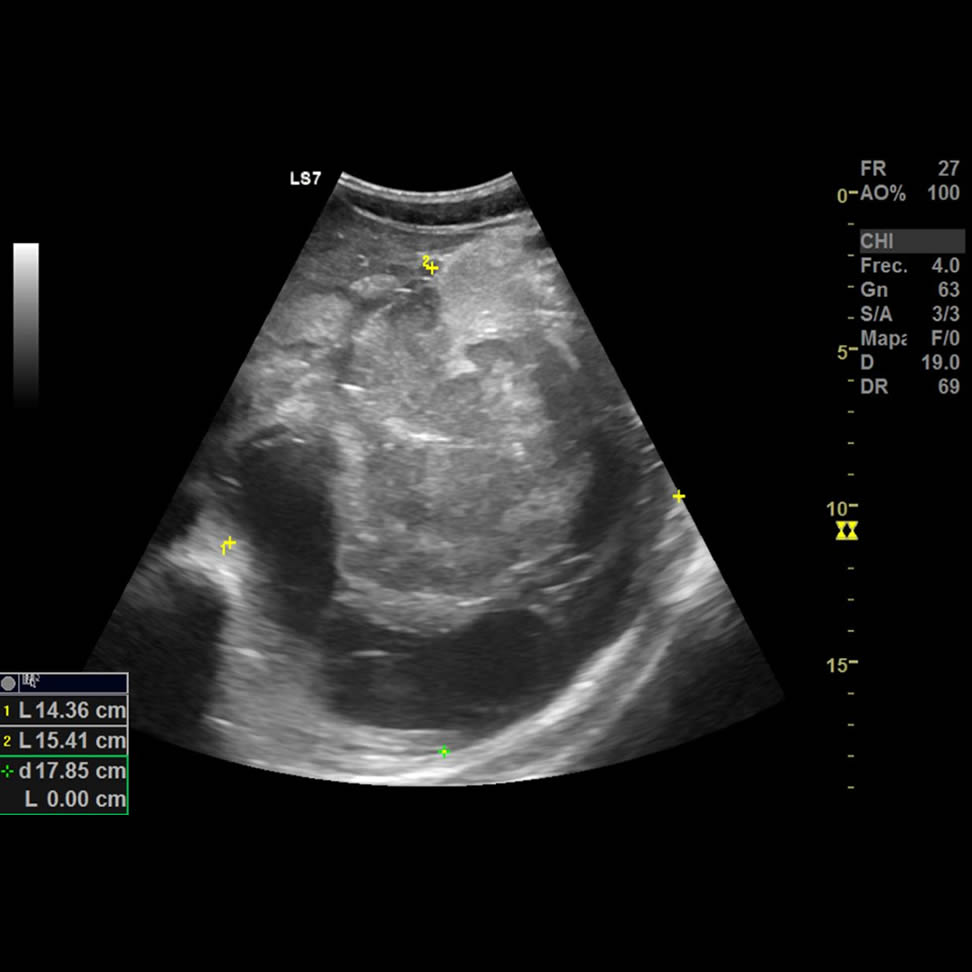

Paciente masculino de 25 años, sano previo, con dolor abdominal